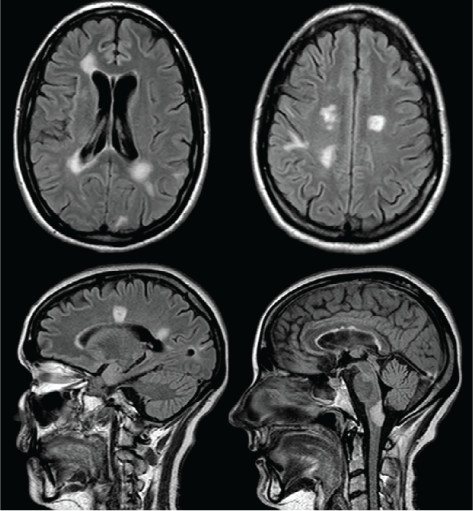

She was transferred to our tertiary-care center for further management. At this time, her EDSS score was 9.5. Findings from extensive blood work performed to rule out other causes of inflammatory lesions in the brain were all negative and included antinuclear antibodies, extractable nuclear antigens, antineutrophil cytoplasmic antibodies, antithyroid antibodies, arbovirus, Lyme, human immunodeficiency virus, hepatitis, toxoplasmosis, cryptococcal antigen, tissue transglutaminase, B12, and serum angiotensin-converting enzyme. Her NMO antibodies were negative. Her cerebrospinal fluid showed slightly elevated protein levels at 466 mg/L (reference range, 200–400 mg/L) and 6 × 106/L nucleated cells. Cerebrospinal fluid cytology, herpes simplex virus polymerase chain reaction, and oligoclonal bands were negative. This lumbar puncture was performed after the long course of corticosteroids. Her MRIs showed multiple tumefactive lesions in the medulla, bilateral periventricular white matter, and white matter of the corona radiata (Figure 1). An expert neuroradiologist (DHL) reviewed previous MRIs and concluded that the findings were consistent with her previous MS diagnosis and with a new tumefactive presentation. Because this was deemed a corticosteroid-resistant relapse, PLEX was initiated 19 days after symptom onset for a total of five exchanges of 3 L each, performed every other day.

Axial and sagittal fluid-attenuated inversion recovery images showing multiple tumefactive lesions in the periventricular white matter, white matter of the corona radiata, and medulla